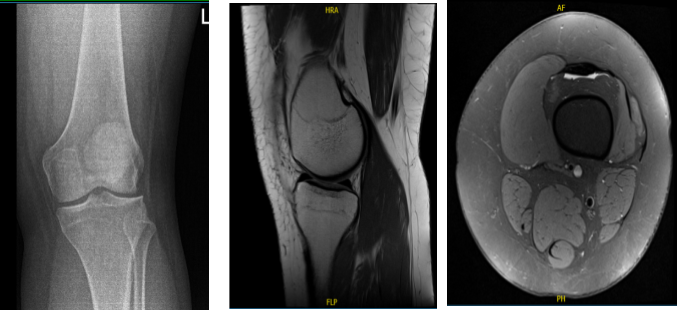

Her X-ray showed no significant degenerative changes and no acute fractures. We agreed to have an MRI which showed a bucket handle tear of the lateral meniscus.

MRI of the left knee